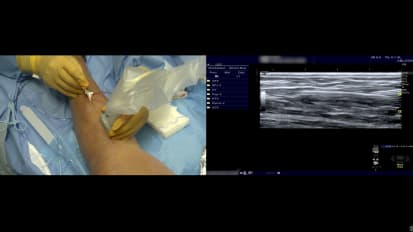

Chapters Transcript Video Left Refluxing Perforating Vein Ablation with Venclose Maven™ Perforator Catheter Featuring: Dr. Jeffrey Carr; Duration: 13 minutes A 46 year old man who has had a very long standing chronic disease of very very strong family history. And he came to me uh complaining of years and years of heaviness, aching, tired, fatigue in his legs, the throbbing and restless legs and cramping. And not to mention, he had over 12 episodes of recurrent thrombophlebitis in both legs. The left leg was worse than the others uh than the right. Um He underwent laser ablation therapy 15 years ago by another provider just of the thigh portion of the great sinus vein, but really did not achieve really any significant improvement over the ensuing years. On his initial duplex ultrasound, we showed closure of that thigh portion of the great sinus vein, but pathologic reflux of bilateral great sap anus and small sinus veins as well as a very large left distal calf perforator of 5.8 centime millimeters and 1942 milliseconds of reflux. Now, he had focal pain over the site of this distal calf perforator that persists despite treatment of his left great sinus vein. And so that's the focus of our intervention today. Uh In addition, because of his recurrent thrombophlebitis is at high risk uh for additional episodes, they've been very painful. Um And he has many superficial vars as well. Uh, that had drained into the superficial system that we will plan on tackling later with phlebectomy. We wanna look at our treatment length that we think we can adopt from that distal end. Yeah, you come, come back, do five. Ok. Just stay right there. That's good. That's good. Ok. So that's do not cross mark that, that's our, that's our safety distance. And now we're gonna move from there to the entrance. We believe that where we think we're gonna angle in on access right about a little more. OK? So just over 22 centimeters or 20 millimeters, this is a five millimeter coil. It's important not to overdo the lidocaine your wheel. Uh These veins are very vasal reactive. So you gotta be very careful, come up very easy and just put a little wheel there and not too much, just enough so that they don't feel the skin neck again. He has a soft, softer skin. The key is to not to move too much with the sonography and just to find it, you can see the tip. Now, I'm not on the edge of the show me the good lumen, the black lumen. There you go more, a little more. So I'm just about to pierce it. I'm gonna poke, poke through a little bit. No looking real. I think I just grabbed some tissue there. How about now? It feels like it. Anybody see. Ok, I am in the vessel. I'm gonna hold really still. I like my assistant to put that in because I'm focusing on not moving an iota and now you say I landed the plane, not at the beginning of the runway, but you know, maybe 1/4 of the way and in Korea just put the wire down and it made it to the edge and it actually made the turn. So it's a looped. It's a little loop. No, it's not loop. It's perfect. It's in the PT. So I'm in the vessel. I'm gonna take my wire out, gonna make a little incision, not my wire, my needle out and then I'm gonna keep that wire right there. We don't wanna lose that position because we, we're pretty pleased that it went in where we hoped I'm gonna make a little skin nick because I don't want resistance when we put the sheath in to pull my wire out. So just a little 11 blade skin nick. And then can you load the space so she'll load this on. I'm just really focusing on not moving that wire and then notice the dilator the distance of the dialer to the sheath. Ok? Because the key is to get the sheet in the dialer is gonna go into that vein, but we're gonna make sure the sheath does. So I'm holding my wire, Casey's gonna show me approaching it. Ok. So we have the dilator in the vein, we have the wire around into the poster tubule. But you can see it's very challenging to know where the sheath begins. And then what's where the sheath and the dilator are in relation on the ultrasound. So that's why it was important to look at how much I'm going to anchor the dilator now. Ok. That's a great view. You can see the double density. I'm gonna just try to advance the sheath in over the dilator here without pushing the dilator and, and that's it. So now my sheet is in and I'm pulling the dilator out and we have that wire in a good position. So I think we can pull everything out, right? We're going to OK. And then we have feedback that we're in the lumen. Wonderful little flesh, please. I'm gonna jiggle just a little. So here I am to the right. I'm not even in it yet. I gotta shallow. My angle of it. Oh, there it is. Right. OK. We're coming into the top into that tributary. Now, you can see the truck, the needle, but I'm off plane. So she's gonna open up the lu in there. I'm not moving right there. I wanna see, I'm gonna aim for her target right there. So I moved laterally and I think right there, I'm in a good position as I enter in. Can you flush that real quick. Just a light little flush. We're going to just flush that again. That's our feedback. It's very challenging. But I think when we flush, we'll be able to see, um, see the tip of the catheter, just light little flush. Ok. That's good. And you see the bubble, so we know where tip is really at the edge of our right where that turn was. So we're in really good position. I'd rather be too far forward than not in the vein. So now we're inserting the maven which has markings on it and the five millimeter tip, I'm anchoring this very firm not to pull back. And I'm really just wanna come in with the maven. You can see it coming in now and I'm gonna go right to that edge and I think that's right where we initially preplanned pretty close. I'm gonna pull back now with the sheath, I'm gonna remove the sheath completely. Very careful not to let the maven come back. It's very lubricious, slippery and it can easily come out if you're not anchoring it. Yeah. So make sure you got dry hands and catheter that we're in good position. I like to note on the skin where we are, you have a number there four on the skin. So it's about, it's just under four and now we're gonna check our distal tip just like we did on the pre and we're gonna try to locate the coil and I could see this many wants to come and point to it, please. So the tip, the plastic tip is right at the junction. Correct, right down there. It's very hard to see it, but it's right there. And 3.5 millimeters from there to, to the coil is the beginning of the coil. So it looks like the coil starts right there. Go ahead and measure that. And that's confirmatory. Yeah. 3.5. We're perfect. So we're very confident that dense white is the beginning is the five millimeter coil. Can you measure the coil itself just to show that we're all on the same page. This is so important to take your time and make sure you know exactly what it is because so I'm gonna put it in there. I'm gonna show I'm pushing it in just to show the coil five millimeter coil. There it is OK. So take that off. So a little pinch here, fill some burn. So you can see my needles perfect. It's going right to the tip and I'm pushing the posterior tibial vein away from my treatment location. Again, I'm gonna pull back before I heat here. I'm a little distal and again, I'm kinda going on all sides of this thing. I'm gonna come back a little bit a lot more just to get this point here. We also want to stay away from the skin is another hazard, five millimeters or greater. Here we go first treatment. So we're getting feedback from the generator. But at the same time, it's important to look at the ultrasound and see if you're getting treatment affect where you think, where you believed it was occurring. So we're exactly where we hoped and thought you could see the e echo density occurring. Often. You'll see a little scintillating or bubbling, boiling of the blood. And this is our second treatment cycle. 22nd cycles. Target is about 100 and 30 °C. You don't feel anything, not a thing. He's enjoying the ride and we're starting to see some echo density, meaning we have treatment effect. We're getting coagulum, we're denuding the endothelium of the vein to destroy it on and create inflammation. So I'm very pleased with this location at the deep and we're well enough away from the posterior tibial vein there. From experience to date. We have, we've been able to inform ourselves about this. We early on in the original study. Um the ID E trial, we worked from one treatment per location to six. We found safety at either one of those uh strategies, but we saw a few pas early on when it was just a one and done uh location. Um I think there are a lot of variables that go into it. Um I believe if you're in the lumen and are absolutely certain, you know, you're gonna deliver the therapy. But uh we've been practicing and recommending up front the six So I'm gonna stop here. We did six. We're gonna recommend six per location up front to get clo the best chance for closure. So I'm gonna be staring down here to pull back five and my and Casey's gonna be looking to see if it matches up what we think on the screen. So here I go, I'm pulling back and that's in the middle of the next one. So we think that's five. You agree? Yeah, there could be, there could, there could be plaques. I'm sorry, there could be slack stored in the catheter. You may not be pulling back. Exactly five. So just kind of be aware of that. You see the poster tibial head flow and you see that's the closed perforator there, you can see it to the top left here where it drained in and we see complete closure uh from the, from the treatments today. And then now I just show the posterior tibial really try to line that out and we have flow. There you go. Now we're really laying it out and it's hard when there's compressed images. So uh do your best. Uh the best is to follow up with these patients. Published December 13, 2024 Created by Related Presenters Jeffrey Carr, MD, FACC, FSCAI Interventional Cardiology, Cardiovascular Disease, Internal MedicineCHRISTUS Trinity Clinic View full profile